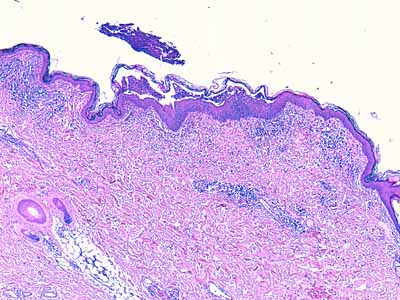

Microscopiquement, plusieurs patrons lésionnels peuvent s’observer dans la leishmaniose cutanée:

- Dermatite d’interface lichénoïde granulomateuse (Photo 15)

- Dermatite d’interface lichénoïde et périannexielle granulomateuse (Photo 16) avec péri-folliculite et adénite sébacée granulomateuses (Photo 18)

- Dermatite interstitielle granulomateuse nodulaire ou diffuse (Photo 17) avec péri-folliculite et adénite sébacée granulomateuses (Photo 18)

- Dermatite périvasculaire superficielle et/ou profonde, pustuleuse, acantholytique ou non (Photo 19)

- Vascularite (Photo 20) (rare)

La composition cellulaire de l’infiltrat inflammatoire, tout particulièrement s’il s’avère riche en macrophages, plasmocytes et granulocytes éosinophiles doit inciter le pathologiste à rechercher des leishmanies intra-cellulaires dans le cytoplasme des macrophages (Photo 21 & 22).

Lorsque les lésions sont riches en éléments parasitaires, le Diagnostic histologique de leishmaniose ne pose pas de problème particulier, mais lorsque le patron lésionnel est moins classique (dermatite périvasculaire pustuleuse acantholytique ou non, ou vascularite) et /ou lorsque les lésions sont pauci-parasitaires, l’examen histologique arrivera difficilement à un diagnostic de certitude, mais plutôt à une forte suspicion histologique de leishmaniose cutanée : il faudra alors compléter l’examen histologique par d’autres examens complémentaires [Photo 23 démarche diagnostique conseillée par LeishVet guidelines for the pratical management of canine leishmaniosis, 2011 (6,7)].

Photos 15 à 22 : Patrons lésionnels rencontrés dans les lésions histologiques de leishmaniose cutanée : Dermatite d’interface lichénoïde granulomateuse (15, HE X100), Dermatite d’interface lichénoïde et périannexielle granulomateuse (16, HE X100), Dermatite interstitielle granulomateuse nodulaire ou diffuse (Photo 17 HE X25) Péri-folliculite et adénite sébacée granulomateuses (18 HE X200), Dermatite périvasculaire superficielle et/ou profonde, pustuleuse, acantholytique ou non (19, HE X25) Vascularite (20, HE X400), Infiltrat inflammatoire riche en macrophages, plasmocytes et granulocytes éosinophiles (21 & 22, HE X1000).